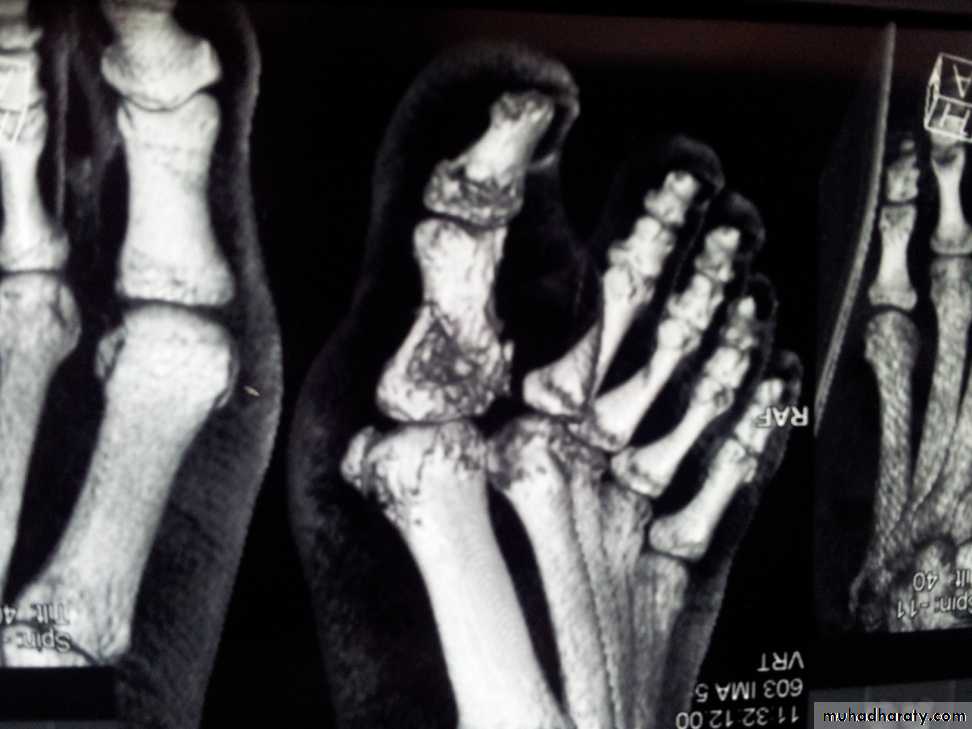

Imaging:

X-Ray: shows area of rarefaction surrounded by sclerosis.

And sometimes with sequestra.

Sinogram helpful to localize the site.

Bone scan: useful for revealing hidden foci of infection.